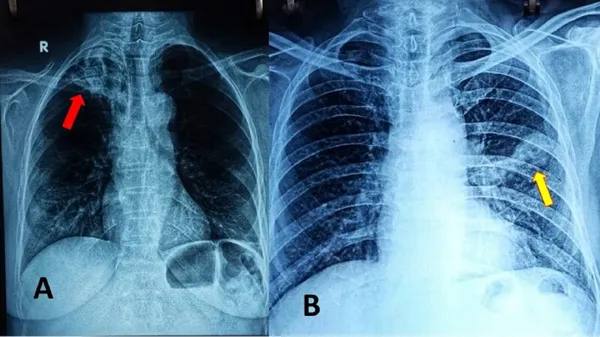

ಈ ಜೋಡಿ ಆಕ್ರಮಣವು ಕಾಕತಾಳೀಯ ಎನ್ನುವುದಕ್ಕಿಂತ ಹೆಚ್ಚಿನ ವಿಷಯವಾಗಿದೆ. ಇದು ಸಿಂಡೆಟಿಕ್ ಸ್ಥಿತಿಯ ಒಂದು ಶ್ರೇಷ್ಠ ನಿದರ್ಶನವಾಗಿದೆ, ಇಲ್ಲಿ ಎರಡು ರೋಗಗಳ ಅಂತರ್‌ಕ್ರಿಯೆ ಯಿಂದಾಗಿ ಉಭಯ ರೋಗಗಳ ಪ್ರಭಾವ ಹೆಚ್ಚಾಗಿ ರೋಗಿಯ ಪರಿಸ್ಥಿತಿಯನ್ನು ಹದಗೆಡಿಸುತ್ತದೆ. ಮೈಕೋಬ್ಯಾಕ್ಟೀರಿಯಂ ಟ್ಯೂಬರ್‌ಕ್ಯುಲೋಸಿಸ್ ಎಂಬ ಬ್ಯಾಕ್ಟೀರಿಯದಿಂದ ಉಂಟಾಗುವ ಟಿಬಿ (ಕ್ಷಯರೋಗ), ಗಾಳಿಯ ಮೂಲಕ ಹರಡುತ್ತದೆ. ಅಲ್ಲದೇ ಪ್ರಾಥಮಿಕವಾಗಿ ಶ್ವಾಸಕೋಶದ ಮೇಲೆ ಪರಿಣಾಮ ಬೀರುತ್ತದೆ. ಜೊತೆಗೆ ಇದು ಇತರ ಅಂಗಗಳಿಗೆ ಹಾನಿ ಮಾಡಬಹುದು. ಇನ್ಸುಲಿನ್ ಪ್ರತಿರೋಧ ಅಥವಾ ಕೊರತೆಯಿಂದಾಗಿ ಸತತ ಉನ್ನತ ಪ್ರಮಾಣದ ರಕ್ತದ ಸಕ್ಕರೆಯಿಂದ ಗುರುತಿಸ ಲಾಗುವ ಮಧುಮೇಹವು ದೇಹದ ರೋಗ ನಿರೋಧಕ ವ್ಯವಸ್ಥೆಯನ್ನು ದುರ್ಬಲ ಗೊಳಿಸುತ್ತದೆ. ಇದರಿಂದ ದೇಹವು ಟಿಬಿಯಂತಹ ಸೋಂಕುಗಳ ವಿರುದ್ಧ ಹೋರಾಡುವುದು ಕಷ್ಟವಾಗುತ್ತದೆ.